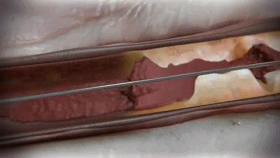

BD的Crosser iQ CTO 旨在幫助腔內(nèi)穿過(guò)外周動(dòng)脈 CTO病變,并且能夠自動(dòng)和選擇性地消融栓塞,既能夠輕松貫穿“堅(jiān)硬”的斑塊,又能不損傷血管。(從下圖中能看到Crosser iQ CTO 可以輕松穿透板材,卻不損傷醫(yī)用手套)

Crosser iQ CTO之所以能夠不損傷血管,這是由于其采用一種獨(dú)特的作用機(jī)制,Crosser iQ CTO能夠?qū)㈦娔鼙晦D(zhuǎn)換成超聲波振動(dòng)能量,導(dǎo)致微氣泡在Crosser iQ CTO導(dǎo)管的頭端膨脹和內(nèi)爆。這會(huì)破壞斑塊的內(nèi)部結(jié)構(gòu),侵蝕CTO的固體表面,從而使醫(yī)生能夠自動(dòng)選擇性地消融斑塊,同時(shí)保持對(duì)彈性組織的無(wú)損傷性。